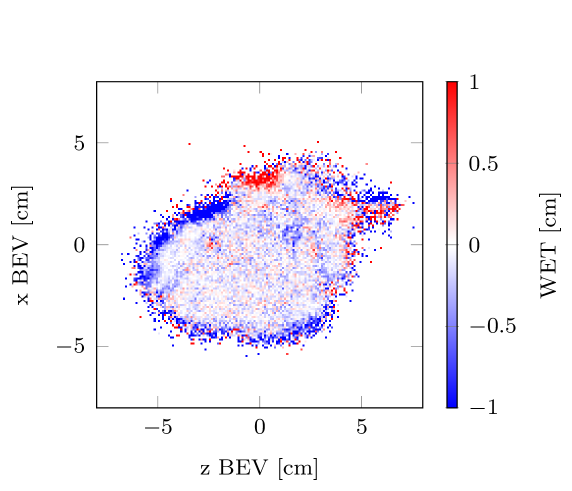

Figure 4 uses an exemplary lung patient (No. 114) to illustrate the distribution of spots with sufficient and not sufficient helium range. For the gantry angle, it is particularly evident that the helium beam is most affected in regions where it must pass through the spine.

Among the examined angles, and appear to be the most suitable, for mixed beam irradiation without range shifters, as they offer a higher minimum residual helium range and a lower percentage of spots with insufficient range. However, may be preferable to since it avoids irradiation through the patient couch. Despite this, for out of the patients analyzed, the minimum residual helium range for a gantry angle of was still below the safety margin. Furthermore, in of the cases, none of the investigated angles provided sufficient range. The most frequently available angle was (/) followed by and (/).